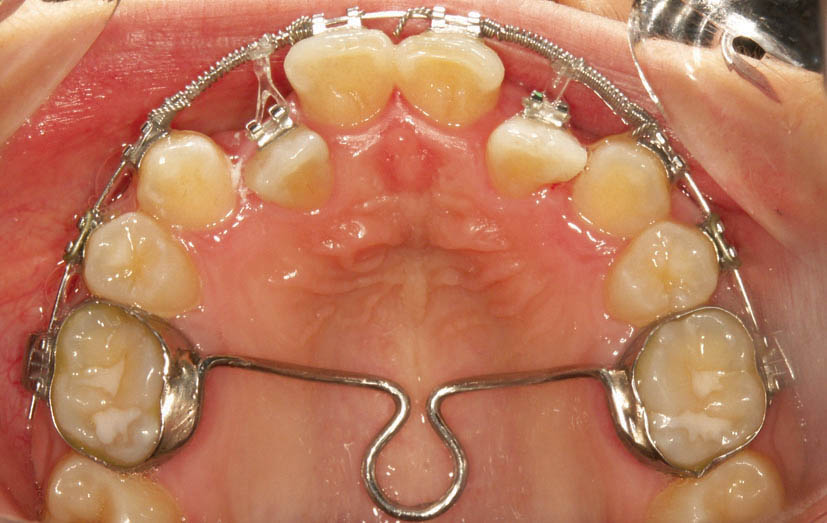

شکل 156-1: بستن فضاهای قدامی به کمک چین الاستیک

اگر استریپ قدامی کردهاید و فضا بین قدامیها ایجاد شده یا بین دندانهای قدامی Space وجود دارد میتوانید چینالاستیک را از براکت کانین تا کانین به مدت یک ماه بگذارید (شکل 156-1) اگر فضا بسته نشد هر ماه Chain Elastic را عوض میکنید تا سرانجام فضا بسته شود. بعد از بسته شدن فضا آن را برمیداریم و به صورت ضربدری از کانین تا کانین با سیم لیگاچور figure ∞ میزنیم تا فضا مجدداً باز نشود. بعد از اینکه فضا را بستیم اگر باز هم چینالاستیک بماند ایجاد کرادینگ میکند.

ضمناً حتماً باید کانینهای دو طرف با سیم لیگاچور بسته شود تا از چرخش آنها جلوگیری گردد. آرچوایر هم 0.020 استیل باشد تا جلوی tilt دیستالی یا مزیالی دندانها گرفته شود.